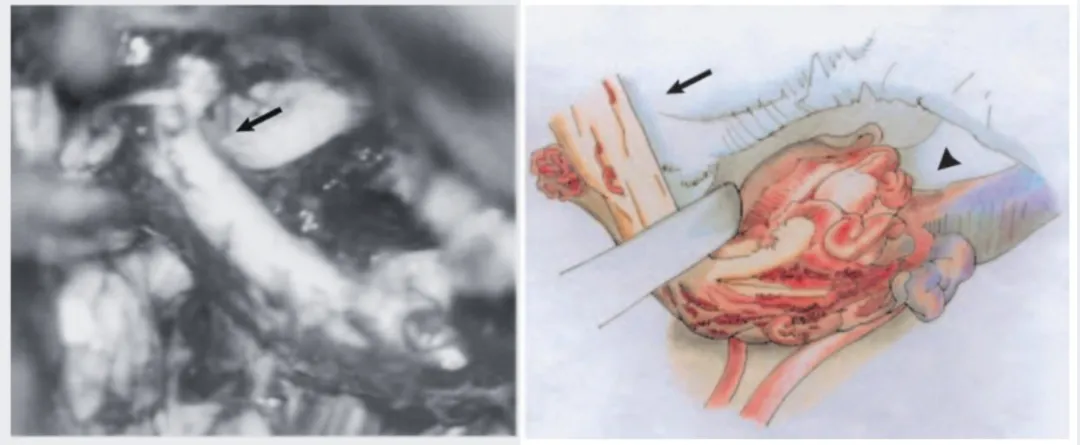

手术过程中,医生观察到三叉神经内部及其周围直至半月神经节区域存在多支病理性血管(图3)。为了能够完整地分离畸形血管团,手术中不得不牺牲了部分三叉神经纤维。

图3 左图:术中照片显示三叉神经根底部(箭头指示)与动静脉畸形关系密切;右图:示意图(由山口幸子绘制),清晰显示三叉神经近端(箭头指示)与畸形血管(箭头端指示)